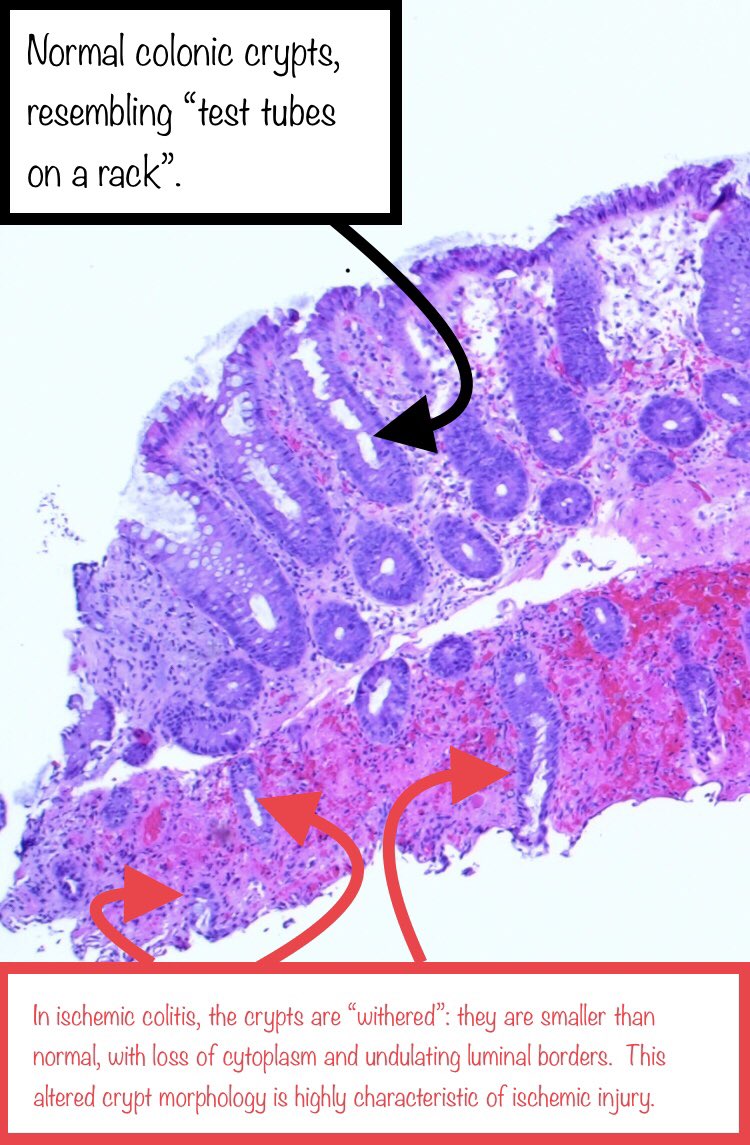

Interesting slide which shows an area of ischemic colitis next to an area of normal colon mucosa.

I thought this was a nice opportunity to show the features of ischemic colitis.

Added some annotations, which may be helpful to those starting out.